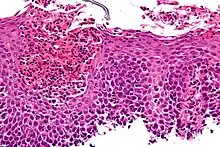

The esophagus is a muscular tube made of both voluntary and involuntary muscles. It is responsible for peristalsis of food. It is about 8 inches long and passes through the diaphragm before entering the stomach. The esophagus is made up of three layers: from the inside out, they are the mucosa, submucosa, muscularis externa. The mucosa, the inner most layer and lining of the esophagus, is composed of stratified squamous epithelium, lamina propria, and muscularis mucosae. At the end of the esophagus is the lower esophageal sphincter, which normally prevents stomach acid from entering the esophagus.

If the sphincter is not sufficiently tight, it may allow acid to enter the esophagus, causing inflammation of one or more layers. Esophagitis may also occur if an infection is present, which may be due to bacteria, viruses, or fungi; or by diseases that affect the immune system.[4]

Although it usually assumed that inflammation from acid reflux is caused by the irritant action on the mucosa by hydrochloric acid, one study suggests that the pathogenesis of reflux esophagitis may be cytokine-mediated.[6]

Eosinophilic esophagitis is caused by a high concentration of eosinophils in the esophagus. The presence of eosinophils in the esophagus may be due to an allergen and is often correlated with GERD. The direction of cause and effect between inflammation and acid reflux is poorly established, with recent studies (in 2016) hinting that reflux does not cause inflammation.[6] This esophagitis can be triggered by allergies to food or to inhaled allergens. This type is still poorly understood.

Lymphocytic esophagitis

Lymphocytic esophagitis is a rare and poorly understood entity associated with an increased amount of lymphocytes in the lining of the esophagus.[1] It was first described in 2006. Disease associations may include Crohn's disease, gastroesophageal reflux disease and coeliac disease. It causes similar changes on endoscopy as eosinophilic esophagitis including esophageal rings, narrow-lumen esophagus, and linear furrows.